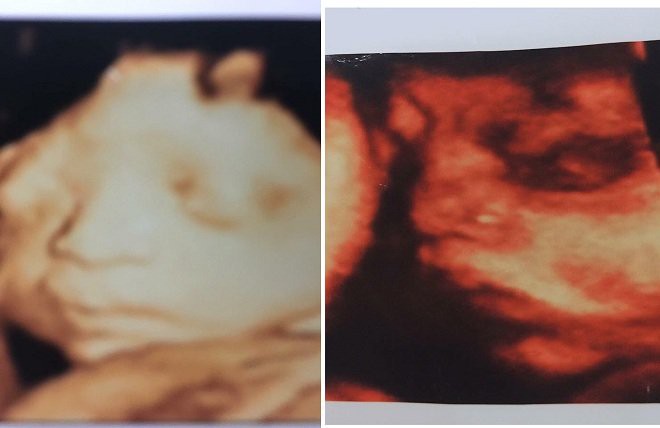

"Tuy nhiên, trong tháng 5, tôi thấy thai nhi của con dâu nhỏ nên nhắn con trai bảo đưa con dâu đi siêu âm nhưng con dâu nói tự đi. Đến trưa, con dâu thông báo đi siêu âm về rồi. Về nhà cũng không cho gia đình xem phiếu siêu âm, chỉ nói là thai khỏe mạnh bình thường. Nghĩ tin con tôi cũng không tra hỏi, mấy mẹ con vẫn đi ăn uống, nói chuyện bình thường. Đến tối 16/6, tôi vẫn nói chuyện qua điện thoại với con dâu", bà M. giãi bày.

Nói về việc con dâu mang bầu, bà M. cho hay, vợ anh L. mang thai đôi, vừa mới nghỉ để chờ sinh, dự tính đến ngày 25 -27/6 sẽ sinh mổ. Tuy nhiên, các cháu bà chưa kịp chào đời, con dâu thông báo thai nhi bị chết lưu khiến gia đình ngỡ ngàng.

Ngoài ra, bà M. cũng khẳng định, con dâu bà có bầu là thật chứ không phải thai giả.

"Con dâu tôi còn sợ rạn bụng nên mua cả kem thoa bụng về để dùng. Có điều, con tôi chửa không to như người khác, nhìn sốt ruột chỉ biết giục con, nhắc con dâu ăn nhưng mỗi lần như thế, con trai tôi lại càu nhàu không muốn mẹ nói vợ", bà M. nhớ lại.